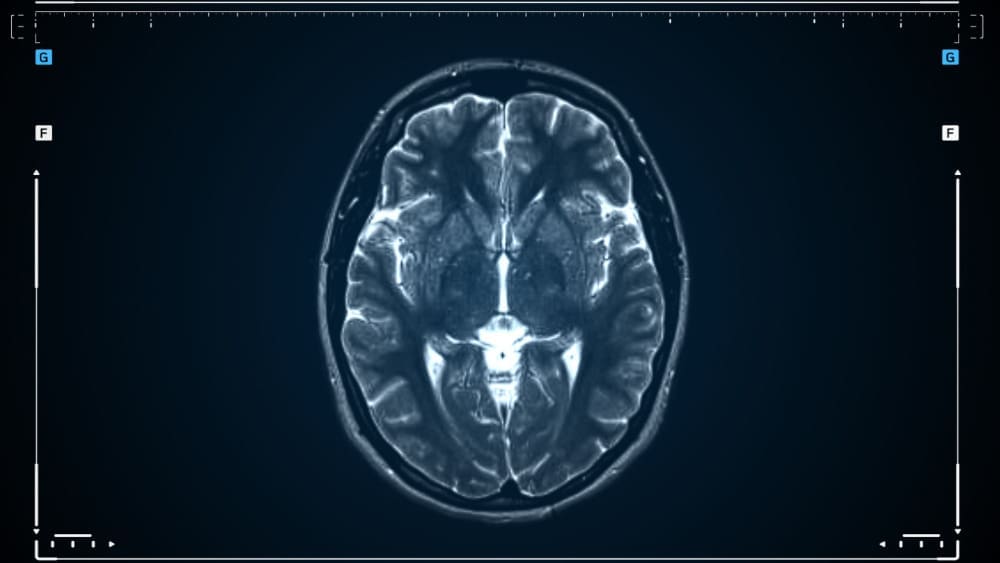

Monitoring: Regular MRI scans can track the tumor’s size and growth. This allows for early action if needed.